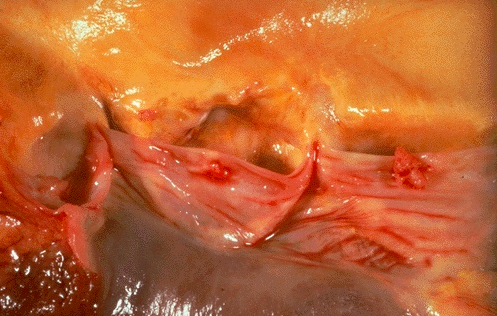

What do you see?

A

- One complication of a transmural MI is rupture of the myocardium. This is most likely to occur in the first week between 3 to 5 days following the initial event, when the myocardium is the softest

- White arrow marks the point of rupture in this anterior-inferior myocardial infarction of the left ventricular free wall and septum

- Note dark red blood clot forming hemopericardium. The hemopericardium can lead to tamponade